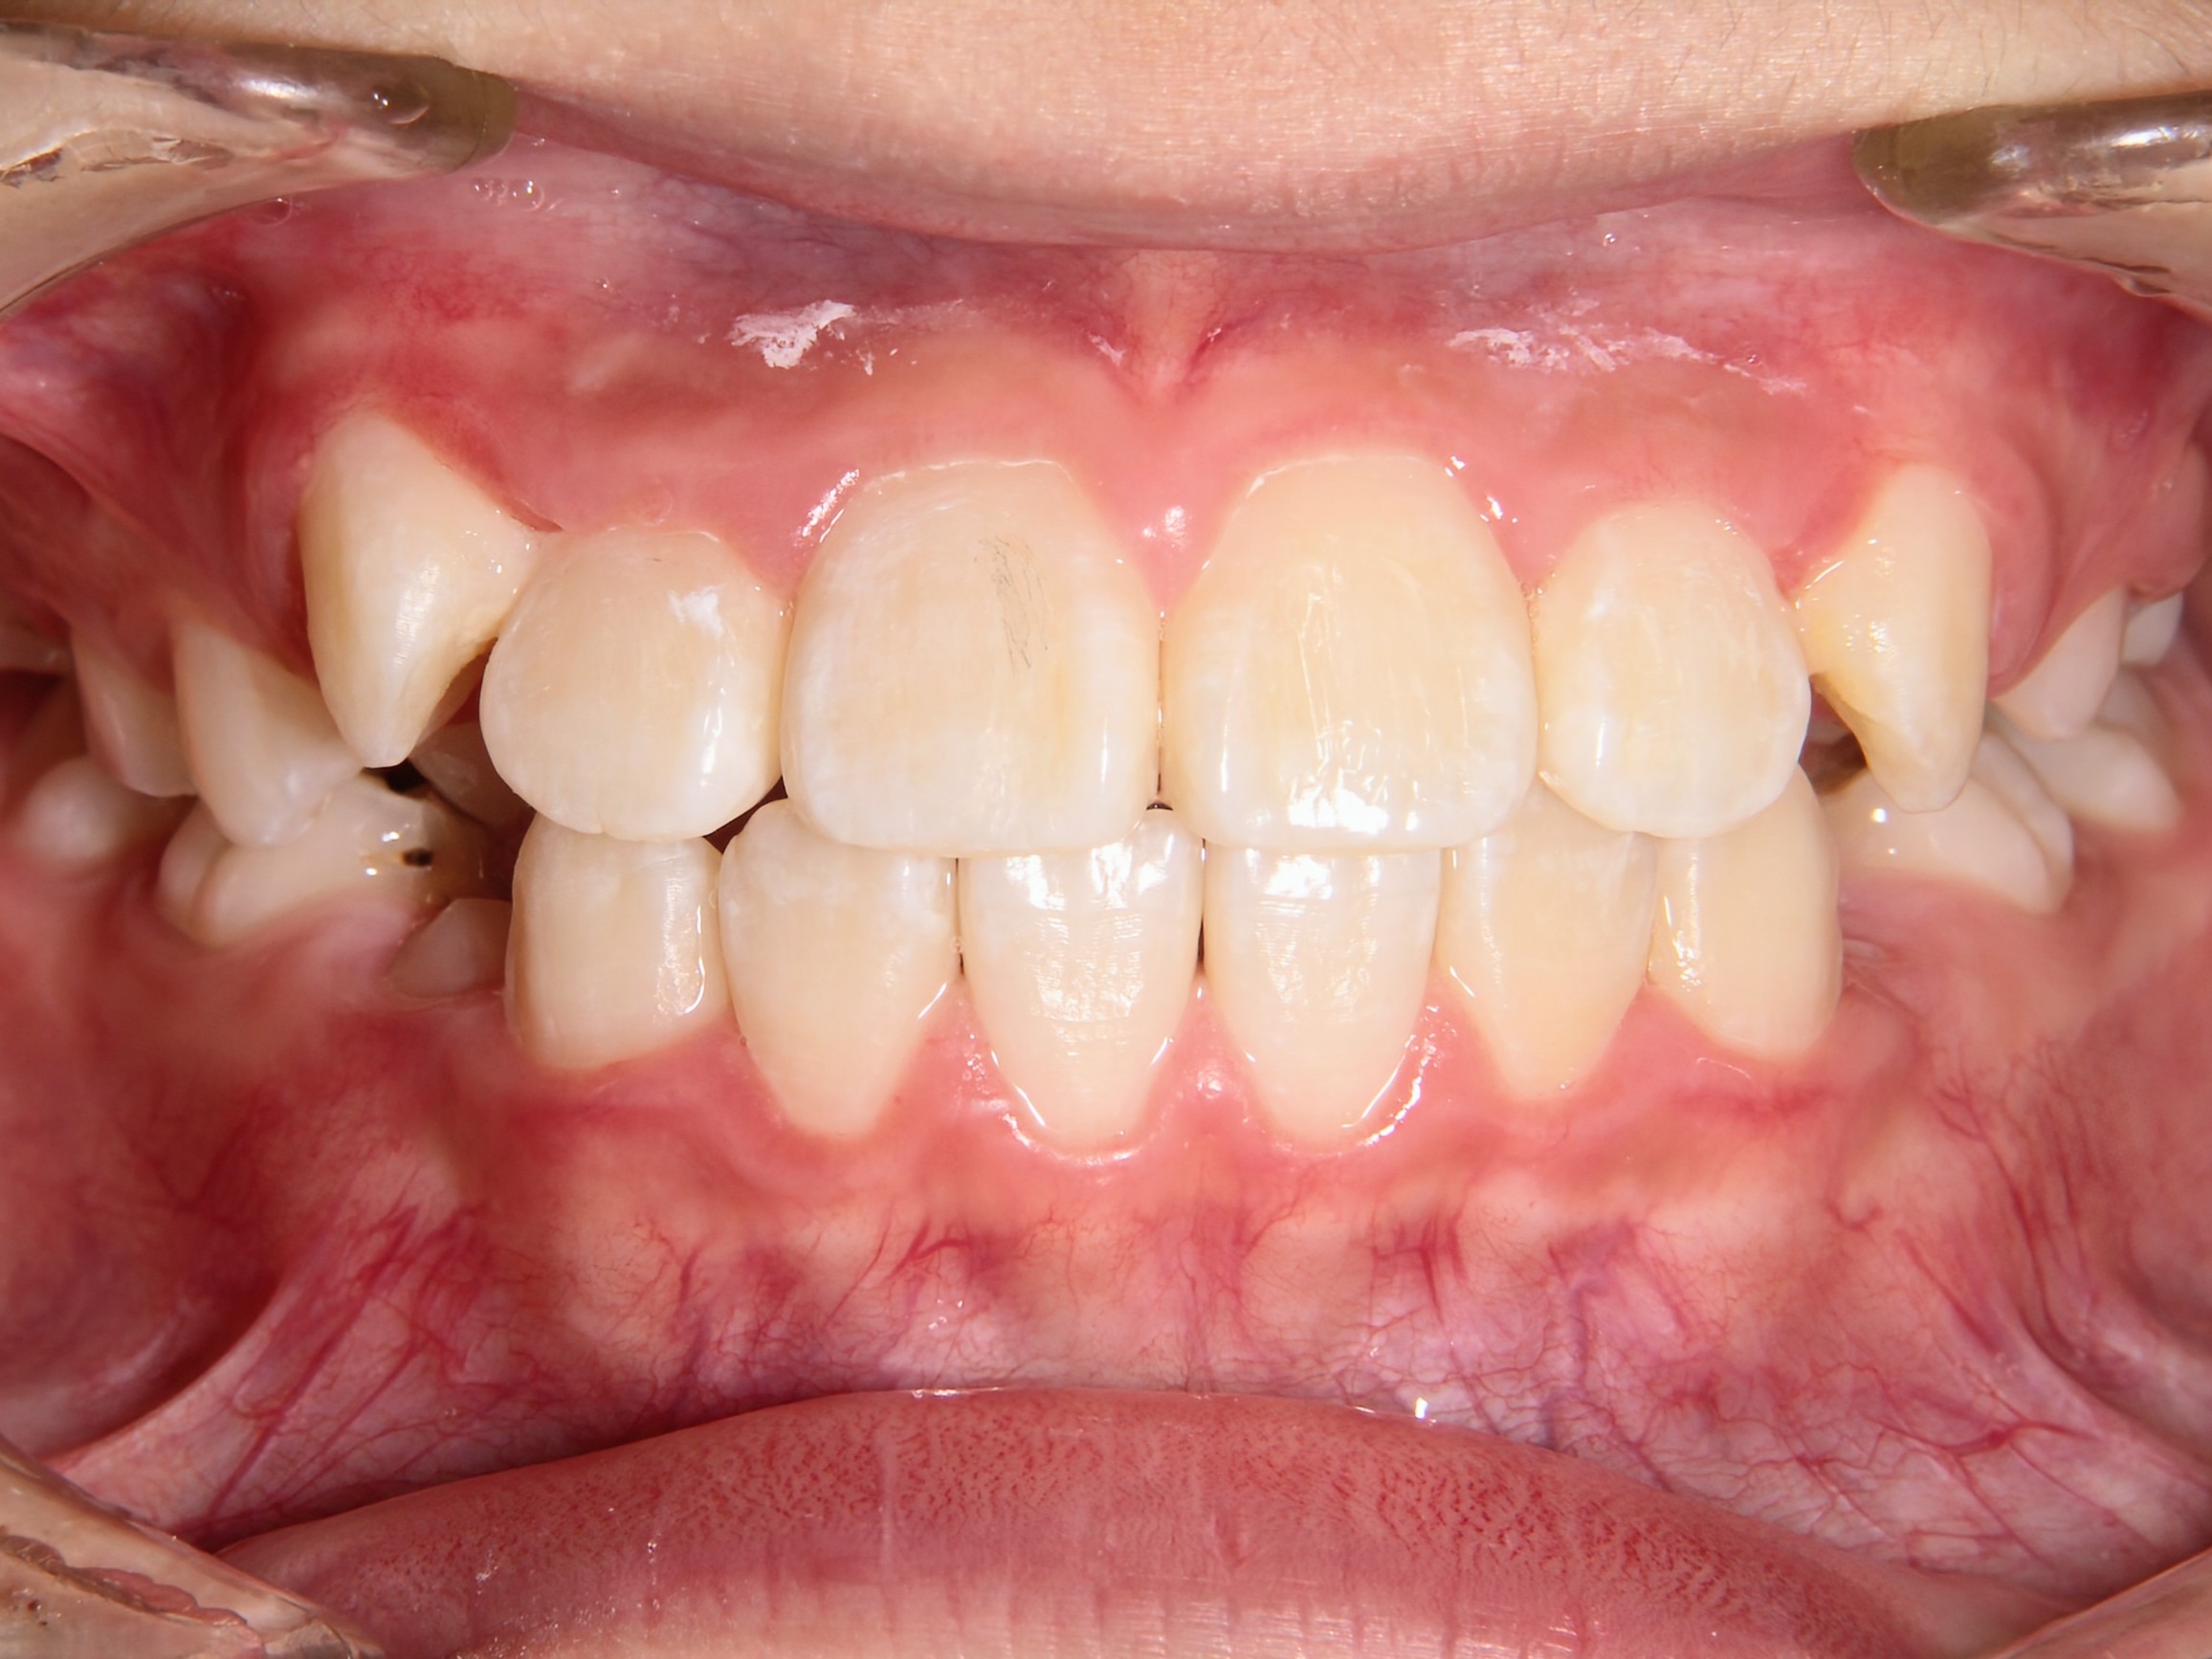

第1期治療終了時

口腔内写真

治療結果

上の前歯のデコボコが改善

上の歯の狭さが改善

目標の永久歯萌出スペースを確保

第2期治療へ移行

上の前歯の裏側に保定装置(Fixリテーナー)を装着し、全ての永久歯萌出後に全顎矯正を行い、全体的な咬み合わせの調整を行います。

経過観察期間:2年7か月